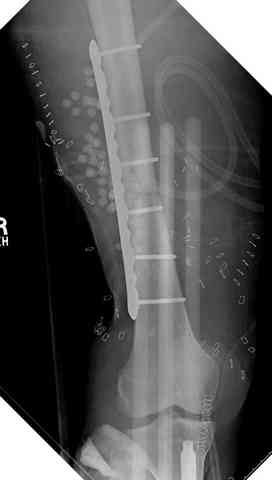

здесь случай с политравмой, перелом зафиксирован наружным фиксатором, после третьей irrigation&debridment фиксация бедра пластиной с последующей кожной пластикой.